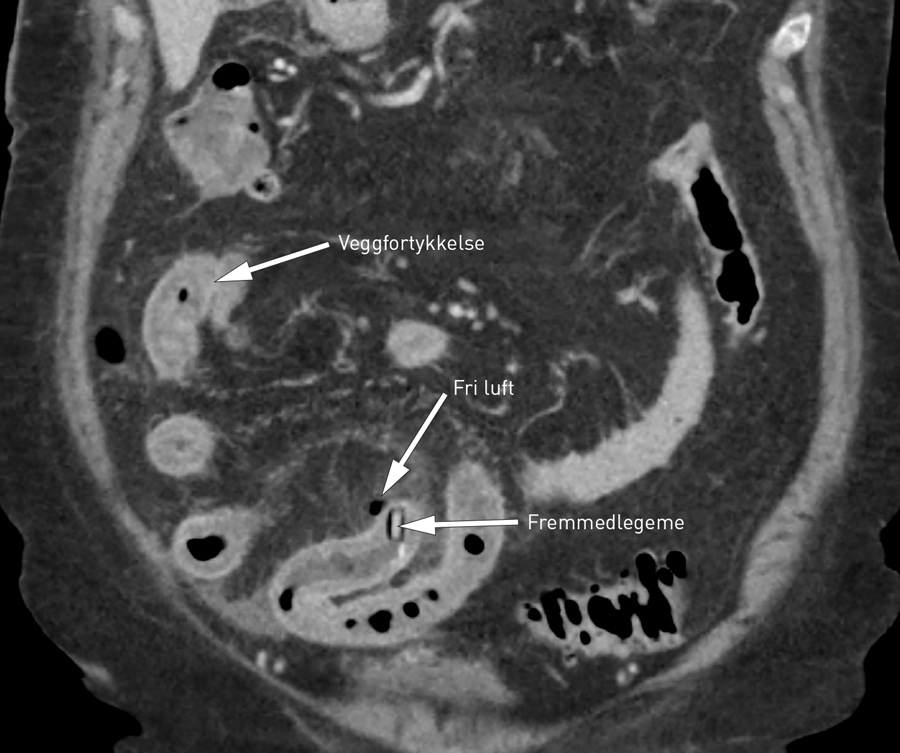

Pasienten ble utredet med laboratorieprøver, EKG og CT abdomen med intravenøs kontrast. Laboratorieverdiene ved innkomst viste forhøyede inflammasjonsprøver, ellers upåfallende verdier: Hb 11,5 g/l (11,4 – 15,3 g/l), leukocytter 19,5 · 10⁹l (3,5 – 8,8 · 10⁹l), CRP 210 mg/l (< 5 mg/l), Na 139 mmol/l (137 – 145 mmol/l), K 4,5 mmol/l (3,6 – 5,0 mmol/l), kreatinin 87 μmol/l (56 – 110 μmol/l), amylase 21 U/l (10 – 60 U/l, bilirubin 18 μmol/l (< 25 μmol/l), alaninaminotransferase (ALAT) 22 U/l (10 – 45 U/l), alkalisk fosfatase (ALP) 82 U/l (35 – 105 U/l). EKG viste sinusrytme uten iskemitegn. CT abdomen med kontrast viste normale basale lungeavsnitt. I abdomen så man tegn til lokale inflammatoriske forandringer i tynntarm med luft utenfor tarmvegg i relasjon til et fremmedlegeme i tarmlumen (fig 1).

Laboratorieprøvene støttet mistanken om en inflammasjon. Med normale hemoglobinverdier var en større blødning lite sannsynlig. Normale funn ved EKG utelukket akutt hjerteinfarkt. Klinisk hadde pasienten diffus peritonitt, i seg selv en klassisk operasjonsindikasjon. I dag gjøres likevel oftest CT abdomen hos sirkulatorisk stabile pasienter før behandling. CT, helst med intravenøs kontrast, er nå førstevalg ved radiologisk utredning av akutte magesmerter og har erstattet røntgen oversikt abdomen. Dersom pasienten har forhøyede kreatininverdier, må man veie risikoen for kontrastindusert forverring av nyresvikt mot tilleggsgevinsten som intravenøs kontrast gir. Eventuelt kan man utføre CT uten kontrast. Oppvæsking før undersøkelsen kan eventuelt redusere risikoen for kontrastindusert nyresvikt. CT er i dag en tilgjengelig og rask undersøkelse og gir ofte klinikeren en presis diagnose og mulighet til å målrette behandlingen. Hos denne pasienten ga kliniske funn og CT-undersøkelse diagnosen og operasjonsindikasjonen.

Klinisk er det ikke mulig å skille tynntarmsperforasjoner fra perforasjoner andre steder i gastrointestinalkanalen. CT abdomen med kontrast er den beste undersøkelsen for raskt å påvise årsaken til akutte tilstander i buken, i dette tilfellet et fremmedlegeme, og å lokalisere tarmperforasjonen (8). Laparotomi med tarmreseksjon er nødvendig. Laparoskopisk intervensjon kan være alternativ metode.